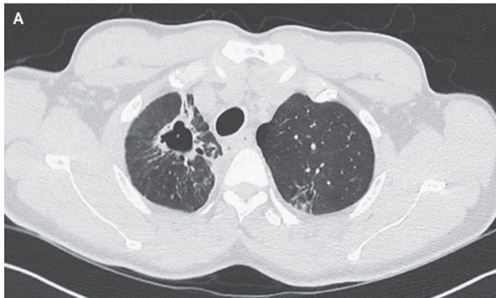

来院16か月前の胸部CTでは治療した肺結核の後遺症である右上葉の空洞が示されていた。